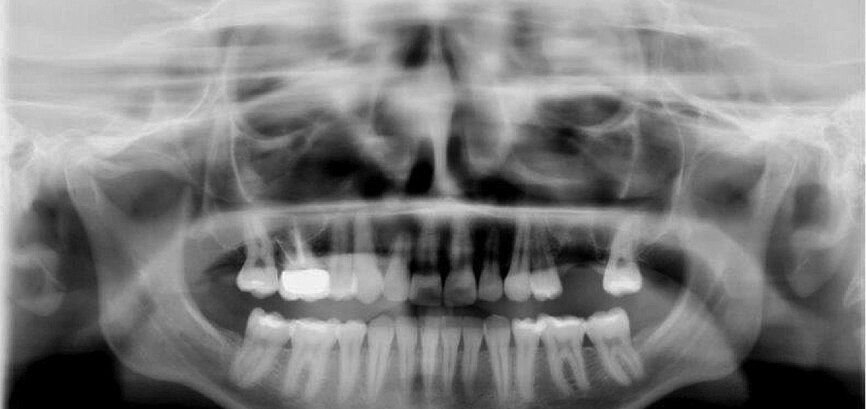

Fig. 14: Dental panoramic tomogram of initial situation.

The first was a 51-year-old patient who smoked 30 cigarettes per day and suffered from diabetes and stress (Figs. 1–8). The second was a 76-year-old male patient in good physical condition who smoked 40 cigarettes per day. He underwent reconstruction of the premaxilla (Figs. 9–13). The third was a healthy female patient of 24 years of age who smoked 20 cigarettes per day. She required a sinus lift in region #25 (Figs. 14–21). The patients were informed of the intended process in detail and signed the surgical protocol containing information concerning possible risks of failure and complications, as well as information on the alloplastic and synthetic materials to be used.

Digital radiographic images were taken at the time of surgery, 24 hours postoperatively and one month later in order to evaluate implant success (Figs. 6, 7, 11, 13, 15 & 20). In none of the patients inflammatory processes were found and all implants remained stable.